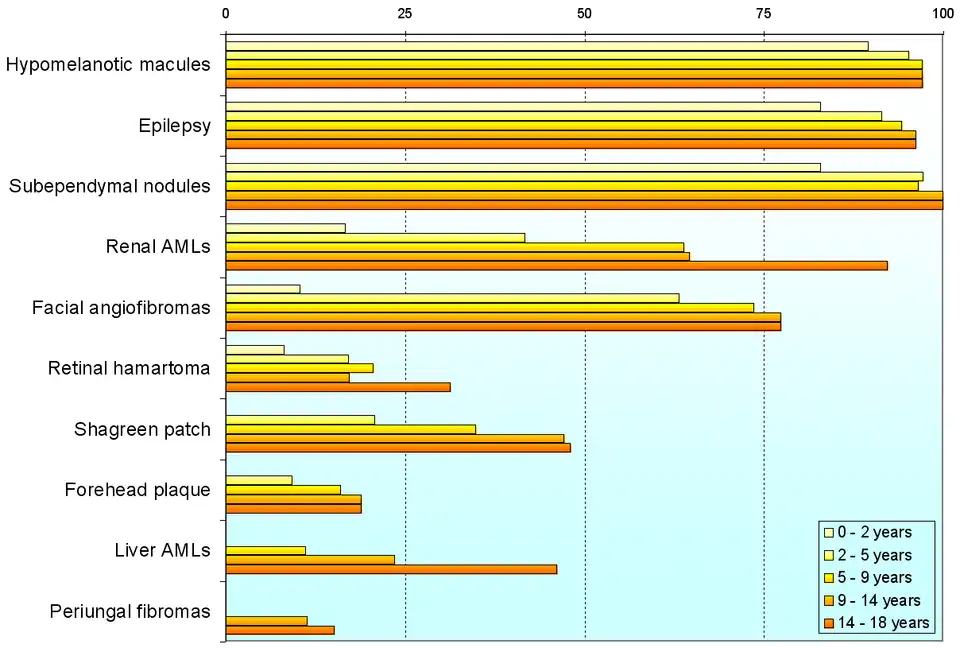

Variability

Individuals with TSC may experience none or all of the clinical signs discussed above. The following table shows the prevalence of some of the clinical signs in individuals diagnosed with TSC.